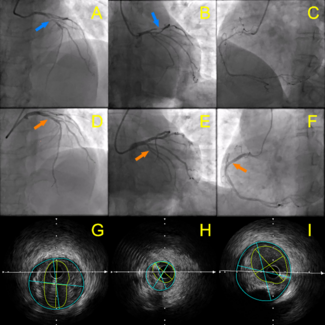

A 73-year-old man, with a previous long drug-eluting stent from the mid-portion of the left main stem artery to proximal left anterior descending artery (LAD), underwent elective coronary angiogram due to worsening anginal symptoms and an...